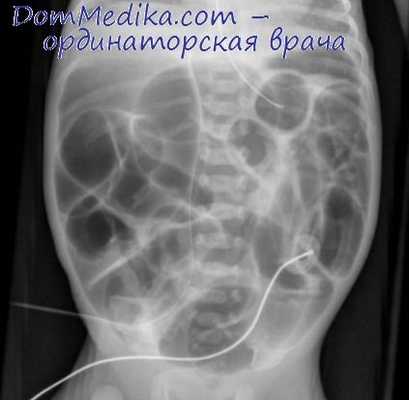

Инструментальные исследования, необходимые для определения синдрома, проведенные до госпитализации в организацию по оказанию паллиативной помощи:при острых состояниях ― простой рентгенологический снимок живота (если есть признаки кишечной непроходимости или скопление большого количества каловых масс в толстом кишечнике).

Рентгенография ОБП при кишечной непроходимости

Если у онкологического больного появились признаки кишечной непроходимости, его нужно срочно госпитализировать в стационар. Самый простой и быстрый способ диагностики кишечной непроходимости — обзорная рентгенография брюшной полости. На снимках можно увидеть раздутые газом участки кишки, скопление жидкости. Один из характерных симптомов — так называемые чаши Клойбера — скопления воздуха и жидкости, которые внешне напоминают перевернутые чаши или буквы «U». [2,12]

Наиболее простой, быстрый и доступный метод диагностики – это обзорная рентгенография органов брюшной полости. На снимках обнаруживаются характерные признаки:

- Чаша Клойбера – видны расширенные петли кишечника в виде куполов, и в них горизонтальный уровень жидкости. Эта картина напоминает перевернутую вверх дном чашу. Чаш может быть несколько, на снимке они наслаиваются друг на друга.

- Кишечные аркады – возникают из-за раздувания газами петель тонкой кишки, в нижних коленах кишки визуализируется горизонтальный уровень жидкости.

- Складки Керкинга – из-за растяжения тощей кишки на рентгенограммах она приобретает вид растянутой пружины.